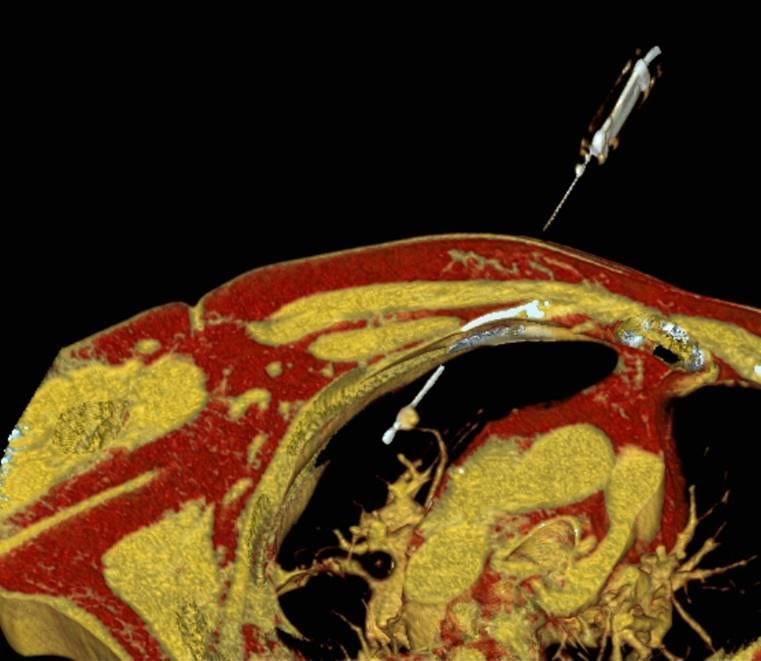

Abbildung: Osteoidosteom (Pfeil) im Schienbein bei einem jungen Patienten. Unter CT-Bildgebung wird ein spezieller Applikatoren unter CT-Bildgebung in das Osteoidosteom eingebracht. Durch Hitze wird dieses effektiv und dauerhaft zerstört.